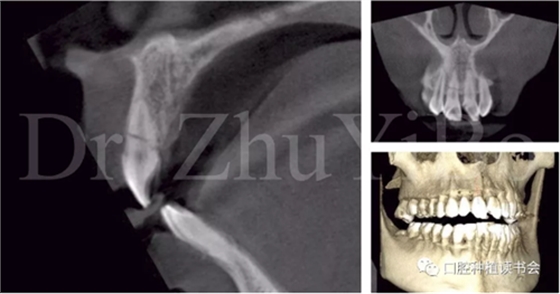

術前cbct顯示:右上中切牙牙根牙槽突類型為一型(圖8)。牙齦為厚型牙齦類型;咬合關系基本正常。

圖8 CBCT:11可見明顯根折線,無法保留